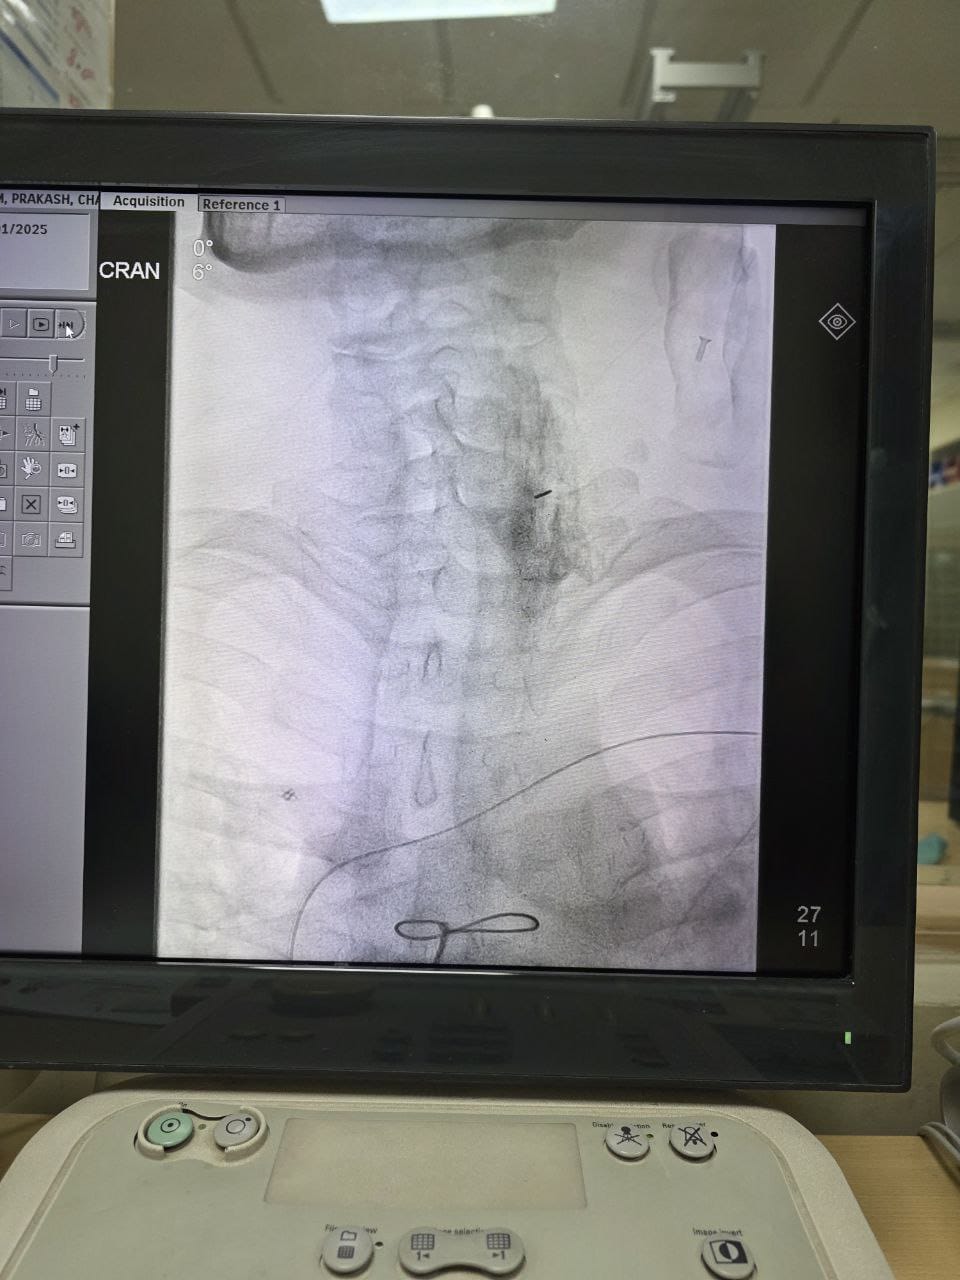

Procedures